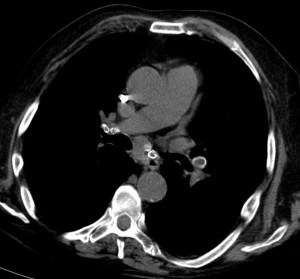

Este signo nos permite diferenciar entre derrame pleural y ascitis en un estudio de TC. Cuando existe una interfase nítida entre líquido y el hígado o el bazo, se trata de ascitis; cuando la interfase no es nítida, se trata de derrame pleural (flecha). El derrame pleural ocupa una posición más posterior y medial, mientras que la ascitis se localiza anterior y lateral al hígado y al bazo.

Esta segunda imagen corresponde a ascitis. Observa como la interfase entre el bazo y el líquido (flecha) es más nítida que en la imagen anterior. También lo es la interfase entre el hígado y el líquido.